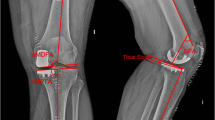

Measurements

Standard radiographs were performed preoperatively and three months postoperatively. Radiographs included a weight-bearing long leg view and a lateral view. The joint line height (JL), the hip knee ankle (HKA), medial proximal tibial angle (MPTA) and the tibial slope (Slope) were measured. The joint line was measured as the angle between the lateral femoral cortex and a line through the most distal point of the femoral condyles. On postoperative radiographs, the same angle is applied with the reference to the lateral femoral cortex. The line through the femoral condyles is referenced to the non-operated lateral condyle. The distance from the most distal point of the implant to this line was measured. These results were defined as the joint line alteration (Fig. 1). This method was described by Herry et al. [8]. Two investigators (LT and PS) measured these parameters twice independently from each other. The intra- and inter-observer accuracy was measured. The mean JL distalization was compared between the two groups. Postoperative outliers of limb alignment and joint line alteration were compared. Limb outliers were defined as a postoperative valgus mal-alignment greater than 182°. JL outliers were defined as a postoperative distalization of more than 2 mm. The surgery time from skin incision to suture was evaluated from all patients.

The demographics and the mean surgery time of both groups are listed in Table 1. The HKA and MPTA change significantly in both groups postoperatively. The joint line was slightly distalized in both groups, there were no significant differences (Table 2). Within the time of follow-up, two revisions occurred in the IB group (5.0%) and two in the IL group (3.2%). The overall revision rate was 3.9% (4 of 103). Two patients had an early aseptic loosening, one patient was revised to a TKA due to ACL instability after trauma and one due to a fracture of the tibia plateau after jumping on a trampoline. No outliers for valgus overcorrection with more than 2° of postoperative valgus were observed in both groups. No significant differences were observed in JL distalization of more than 2 mm between the two groups (32.5% IB vs. 33.3% IL, p = 0.553) (Table 3). The inter-observer accuracy was 0.922 and the intra-observer accuracy was 0.953.

The alternation of the natural joint line has an effect on the mechanics and kinematics of the joint. Biomechanical studies showed a higher load on the tibial tray with a deep tibia resection [21,22,23]. Joint space elevation leads to higher strains in the contralateral femorotibial compartment, thus progression of OA in the lateral compartment might occur [6]. In contrast to that, a distalization of the joint line of 4 mm increases the tibial strain up to 13 and 35%. In addition, it is known that a too distal tibia placement correlates with less resistance to compression forces. Early loosening of the tibial component may be the consequence [24]. Another benefit of an anatomical reconstruction of the joint line is the potential conversion of an UKA into a TKA. Distalization of the joint line accompanies with more bone loss and a potential need for augmentation [8, 25]. In a retrospective multicenter study of 559 medial UKAs, Chatellard et al. determined that a severe distalization of the joint is associated with decreased prosthesis survival [6]. Herry et al. reported postoperative findings after UKA with robotic-assisted surgery with the NAVIO system and a conventional technique. The distalization of the joint line in the robotic group was 1.4 mm. The range goes from −3 to 6 mm [8]. Klasan et al. reported a distalization of the joint line with the MAKO system of 1.5 mm (range: −0.6 mm to 4 mm) [20]. These results reflect our findings. We measured a mean distalization of the joint line in the IB robotic arm group of about 1.8 mm (range: 0 to 3.7 mm) compared to the IL robotic hand-piece group of about 1.3 mm (range: −2.5 to 5.7) (Table 2). All reported results of robotic-assisted UKA are located within 2 mm distalization. Thus, the joint line was reconstructed precisely. The scattering of the values with the IB robotic system is lower compared to the IL robotic system both in literature and in this study. However, both groups present about 33% outlier of joint line distalization of more than 2 mm.

It is known that a slight varus under-correction of the overall limb alignment and the MPTA leads to superior results in UKA [7]. An overcorrection to valgus alignment triggers an early osteoarthritis of the lateral compartment as well as chronical medial collateral ligament (MCL) pain [6, 34, 35]. Preoperative risk factors for postoperative valgus alignment are, e.g., a smaller LDFA and a higher MPTA [36]. These valgus-associated morphotypes are particularly difficult to treat with conventional mobile bearing UKAs. In this study, the mean postoperative MPTA was identical in between groups with 89°, whereas the standard deviation was slightly higher in the IL robotic group. This might indicate a higher accuracy in the IB robotic group, whereas the difference is within the range of measurement inaccuracy. In both groups, the MPTA was in the radiological safe zone [6]. The mean postoperative HKA in the IB robotic arm group was 178° varus and 178° varus in the IL robotic hand-piece group. The range in the IB group was 171° to 181° and in the IL group 170° to 182°. No overcorrection to a valgus alignment (HKA > 182°) was observed in both groups (Table 3). With robotic-assisted techniques, the surgeon has objective control over the postoperative limb alignment. These results are comparable to the robotic literature [37]. Batailler et al. reported a postoperative HKA of 175.2° (range: 170.8–185.6°) and a 16% limb outlier rate with the IL robotic system [9]. Outliers were defined as a HKA > 180° or < 176°. An explicit calculation of valgus overcorrection did not happen. The pre- and postoperative MPTA was not specified. Gaudiani et al. and Kayani et al. reported similar results with the IB robotic system. The mean postoperative HKA was 177.2° and 178.4°, respectively [10, 38]. The MPTA was not measured of both authors. The choice of robotic system does not seem to have any impact on the postoperative alignment.